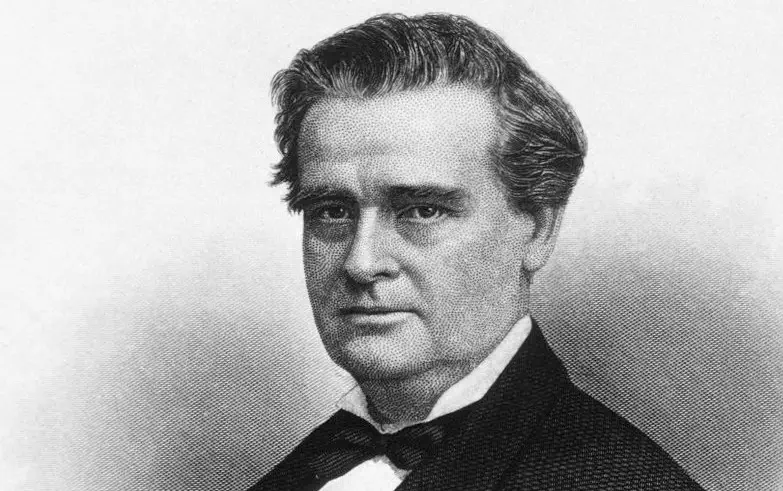

Operace otrokyní zaživa a bez anestezie

James Marion Sims byl alabamský chirurg a gynekolog, který se nechvalně proslavil svými experimenty na černošských otrokyních. Jeho cílem bylo najít způsob, jak zabránit trvalým komplikacím vleklých porodů. Skutečně se mu podařilo určitých chirurgických inovací dosáhnout, avšak za cenu utrpení mnoha žen.

Sims prováděl na ženách operace bez anestezie. Jednak z toho důvodu, že anestezie byla v jeho době poměrně nová, a pak také proto, že podle jeho slov „nešlo o tolik bolestivé zákroky“. Ženy, které operoval, byly černošské otrokyně, jejichž těla nebyla považována za jejich vlastní. Byly pouhým majetkem, se kterým si Sims mohl prakticky dělat, co chtěl. A přestože tvrdil, že otrokyně s jeho experimenty souhlasily, má se za to, že tomu tak jistě nebylo. Sice jim podával alespoň opiáty, jenže ty nebyly dost silné, aby utlumily veškerou bolest. Navíc se na nich pak otrokyně stávaly závislými.